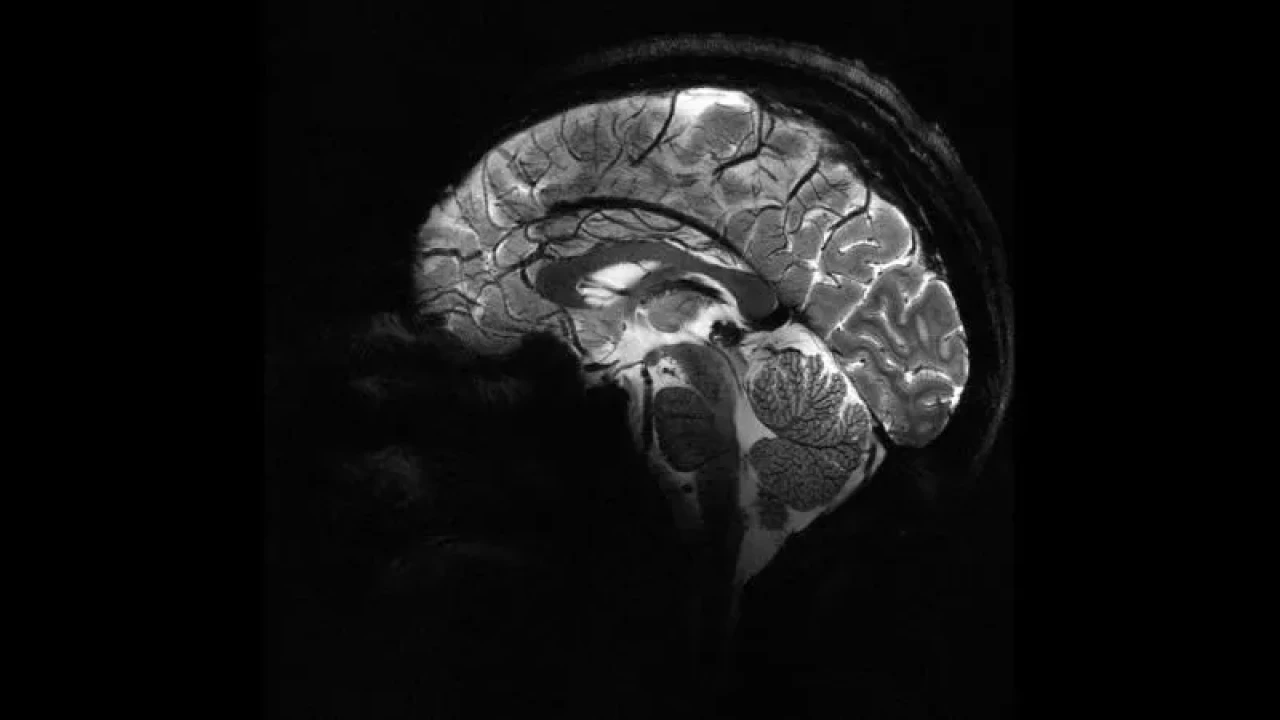

Dil, Zekâ ve Sosyal Algı: Bilim İnsanları İnsan Beynindeki Gizli Gücü Ortaya Çıkardı

Oxford ve Aix-Marseille Üniversiteleri'nin araştırması, insan beyninin eşsizliğinin temporal lobda yattığını belirledi. Çalışma, dil işleme ve sosyal zekâ açısından hayati öneme sahip olan bu bölgenin, diğer primatlarla karşılaştırıldığında daha gelişmiş bağlantılara sahip olduğunu ortaya koydu.

Oxford ve Aix-Marseille Üniversiteleri’nin ortak çalışması, insan beyninin evrimsel olarak ne kadar özel bir yapıya sahip olduğunu bir kez daha gözler önüne serdi. Yeni araştırma, sosyal zekâ, dil işleme ve duyu entegrasyonunda hayati rol oynayan temporal lobun, insan beyninin en ayırt edici bölgesi olduğunu ortaya koydu.

Manyetik rezonans görüntüleme (MRI) teknikleriyle yürütülen çalışmada, beyindeki beyaz madde bağlantıları incelendi. Bu bağlantılar, beyin hücreleri arasındaki iletişimi sağlayarak, zihinsel süreçlerin nasıl çalıştığına dair hayati bilgiler sunuyor.